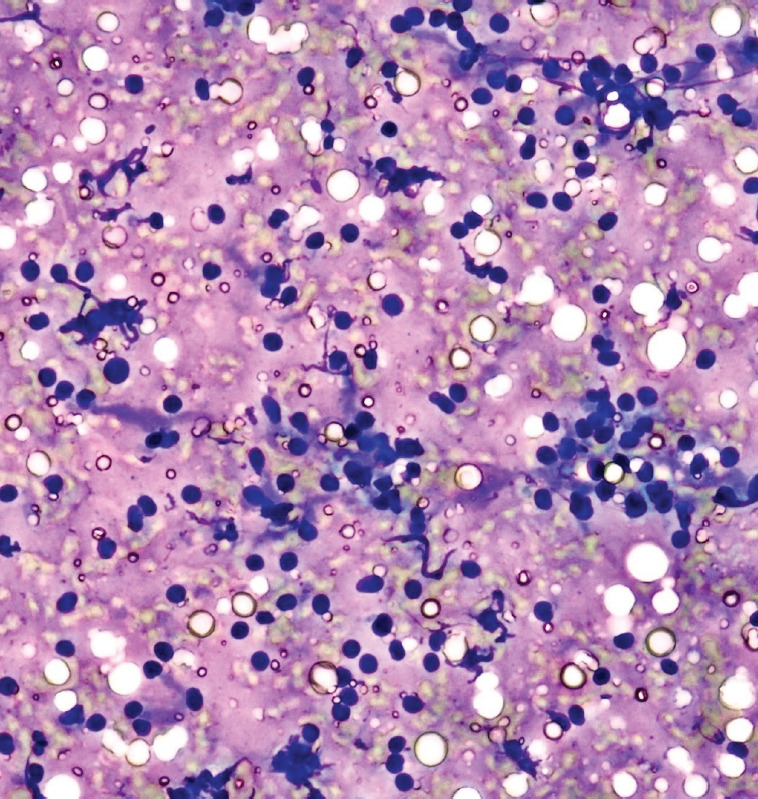

背景/目的:内镜超声引导下细针活检(EUS-FNB)是胰腺实体瘤组织采集的重要工具。细胞学家的快速现场评估(ROSE)确保了诊断的准确性。然而,ROSE的普遍应用受到其可用性的限制。因此,我们的目的是研究由训练有素的内窥镜技师(IRCETE)根据室内细胞学评估结果确定手术结束的可行性。方法:对3名超声医师进行胰腺常见肿瘤细胞学诊断的培训。培训结束后,根据IRCETE结果决定终止EUS-FNB。将诊断的准确性、诊断类别的符合率和样本充分性与委员会认证细胞学家和宏观现场评估(MOSE)的结果进行比较。结果:本组共纳入65例实体性胰腺肿瘤患者,其中大部分为恶性肿瘤(86.2%)。当基于IRCETE确定手术结束时,诊断准确率为90.8%,而MOSE和细胞学家分别为87.7%和98.5% (p=0.060)。根据细胞学家的结果,IRCETE诊断类别解释的准确率为97.3%。结论:在没有ROSE的情况下,IRCETE可以作为MOSE的补充替代方法,具有较高的准确率。

Results: We enrolled 65 patients with solid pancreatic tumors, most of whom were malignant (86.2%). The diagnostic accuracy was 90.8% when the end of the procedure was determined based on IRCETE, compared to 87.7% and 98.5% when determined by MOSE and cytologists, respectively (p=0.060). Based on the cytologists' results, the accuracy of IRCETE in diagnostic category interpretation was 97.3%.